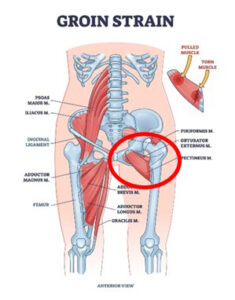

Causes of Spasms of the Pectineus and Adductors:

- Muscular injuries of the adductors, the iliopsoas muscle, and abdominal musculature are the most frequent causes of acute groin pain in sportsmen and sportswomen.

- Spasms in your pectineus muscle are also a common cause of groin pain and are often overlooked.

- Pectineus pain often stems from an injured groin muscle. Common causes include running, kicking a soccer ball, riding a horse, and sitting with a crossed leg.

- Groin pain is any discomfort in the area between your abdomen and thigh, located where your abdomen ends, and your legs begin.

- Localized pain on the pubic bone, in the groin area, on one side or the other, is a primary indication of injury to the pectineus.

- Pain on palpation of the involved muscle and pain on adduction (moving your legs closer together against resistance) is also an indication of injury to the pectineus.

You are trying to be pressing close to your pubic bone, which is shown in the graphic above.